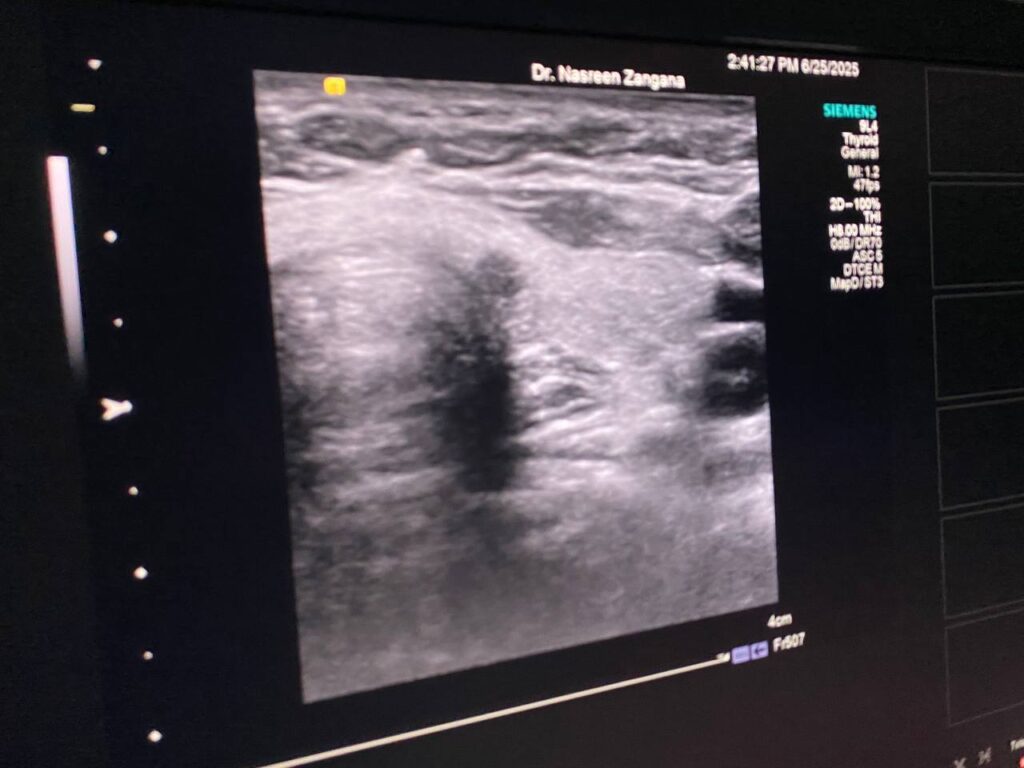

in the left sided of the isthmus presence of two hypoechoic masses , size 3.2×3.3mm, it has indistinct margin , suspicious nodule can not be exclude for further study , the other mass 3.6×2.4mm more regular , mostly lymph node , please for further study TIRADS U4